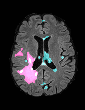

In recent years, data-driven machine learning (ML) methods have revolutionized the computer vision community by providing novel efficient solutions to many unsolved (medical) image analysis problems. However, due to the increasing privacy concerns and data fragmentation on many different sites, existing medical data are not fully utilized, thus limiting the potential of ML. Federated learning (FL) enables multiple parties to collaboratively train a ML model without exchanging local data. However, data heterogeneity (non-IID) among the distributed clients is yet a challenge. To this end, we propose a novel federated method, denoted Federated Disentanglement (FedDis), to disentangle the parameter space into shape and appearance, and only share the shape parameter with the clients. FedDis is based on the assumption that the anatomical structure in brain MRI images is similar across multiple institutions, and sharing the shape knowledge would be beneficial in anomaly detection. In this paper, we leverage healthy brain scans of 623 subjects from multiple sites with real data (OASIS, ADNI) in a privacy-preserving fashion to learn a model of normal anatomy, that allows to segment abnormal structures. We demonstrate a superior performance of FedDis on real pathological databases containing 109 subjects; two publicly available MS Lesions (MSLUB, MSISBI), and an in-house database with MS and Glioblastoma (MSI and GBI). FedDis achieved an average dice performance of 0.38, outperforming the state-of-the-art (SOTA) auto-encoder by 42% and the SOTA federated method by 11%. Further, we illustrate that FedDis learns a shape embedding that is orthogonal to the appearance and consistent under different intensity augmentations.